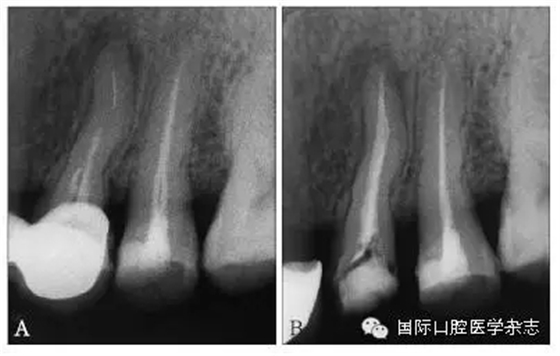

3.2.1 牙本質(zhì)厚度評(píng)估 取出分離器械需要損失部分牙本質(zhì),牙本質(zhì)的損失量包括縱向損失和橫向損失。縱向損失決定于取出時(shí)分離器械冠方末端需要暴露的長(zhǎng)度,橫向損失決定于分離器械的斷端直徑以及選用取出器械的方法(如超聲法或是環(huán)鉆法等)。牙本質(zhì)損失量過(guò)多會(huì)導(dǎo)致根管穿孔、根管折斷等并發(fā)癥[7](圖3)。

A:紅色及綠色的部分分別表示用改良GG鉆及超聲工作尖去除牙本質(zhì)的量;B:MicroCT掃描圖像顯示取出下頜第一磨牙近頰根管中分離器械后,導(dǎo)致了根管穿孔。

圖 3 取分離器械過(guò)程中會(huì)導(dǎo)致牙本質(zhì)損失,甚至穿孔等并發(fā)癥

取出分離器械后,根管壁的殘余牙本質(zhì)厚度是影響牙根抵抗力的重要因素,因而,可以認(rèn)為殘余牙本質(zhì)的厚度是影響分離器械取出與否的最重要的因素之一[8]。

目前,對(duì)于分離器械周?chē)辣举|(zhì)厚度的評(píng)估以及取出后殘余牙本質(zhì)厚度的預(yù)測(cè)主要需借助影像學(xué)檢查,例如根尖片、錐形束CT(cone beamcomputed tomography,CBCT)圖像等。傳統(tǒng)的平行投照的根尖片無(wú)法反映三維立體結(jié)構(gòu),且往往存在解剖結(jié)構(gòu)影像的重疊,不利于臨床判斷,具有一定的局限性。多位學(xué)者[10]的研究表明:平行投照的根尖片會(huì)高估實(shí)際的牙本質(zhì)壁的厚度。一些學(xué)者[11-12]的研究表明:當(dāng)分離器械位于上頜第一磨牙近中根管時(shí),采用成角投照(21°)的拍攝技術(shù)與平行投照技術(shù)得到的X線(xiàn)片相比,能更準(zhǔn)確地評(píng)估牙本質(zhì)的厚度,為分離器械取出與否提供指導(dǎo)(圖4)。近年來(lái),CBCT在牙髓病學(xué)中的應(yīng)用越來(lái)越廣泛,由于CBCT能清楚地反映牙及牙根周?chē)M織的三維立體結(jié)構(gòu),為牙本質(zhì)厚度的評(píng)估與預(yù)測(cè)提供了可行性(圖5);因此,CBCT在器械分離的病例術(shù)前風(fēng)險(xiǎn)評(píng)估方面具有較好的應(yīng)用前景。

A、B:采用平行投照技術(shù)獲得的圖像,模擬取出分離器械后殘余牙本質(zhì)的厚度,分離器械分別位于根管口下3 mm和5 mm;C、D:采用成角投照技術(shù)獲得的圖像,模擬取出分離器械后殘余牙本質(zhì)的厚度,分離器械分別位于根管口下3 mm和5 mm。

圖 4 平行投照與成角投照拍攝技術(shù)對(duì)牙本質(zhì)厚度的評(píng)估

圖 5 使用CBCT評(píng)估分離器械周?chē)辣举|(zhì)厚度